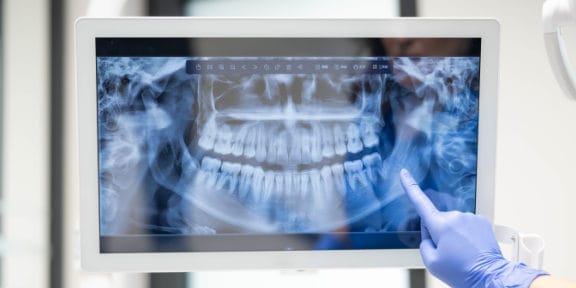

Digital X-Rays

We use digital x-rays to reduce the amount of radiation you get every time we take an x-ray. We only take x-rays of locations that are indicated and attempt to keep the number of x-rays to a minimum, while still allowing for proper diagnosis.

X-rays play an invaluable role in the diagnosis of dental problems, as well as provide a clear picture for a dentist to accurately diagnose and provide the necessary treatment.

We place a small sensor in your mouth. The sensor is connected to a computer by a thin wire. Next, an x-ray beam is sent through your teeth and into the sensor, which records the image of your teeth and sends it to the computer. The sensor can then be repositioned to image other sections of your teeth.

The digital dental x-ray system is more sensitive than dental x-ray film systems, so your exposure to x-rays is cut by as much as 90 percent. The large and color-enhanced images let you see what your dentist sees, so it's easier for you to understand how your dentist will treat your teeth. Your dental checkups take less time, and it's fun to watch this system work! Most patients are amazed.